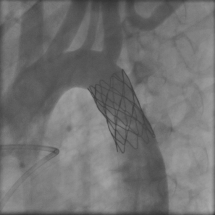

In the past, coarctation of the aorta repair involved heart surgery followed by five to seven days in the hospital for recovery. Today, heart specialists can correct coarctation in many patients without surgery, using a procedure called cardiac catheterization. In the procedure, a thin, flexible tube is threaded through a blood vessel to the heart, where it is used to insert a specially designed stent — a small, metal mesh tube — in the narrowed area of the aorta.

The size of the restricted aorta is measured and an appropriately sized stent, or expandable metal tube, is selected. Sometimes, more than one stent is needed for the repair. Occasionally there will be a weakening of the aortic wall, called an aneurysm, associated with the narrowing. In these cases, a fabric-covered stent may be used to repair both problems. If the narrowing is too close to the head and neck vessels, stent repair may not be possible. In these cases, surgical repair is necessary and will be scheduled for another time.

The stent is placed over a deflated balloon at the catheter's tip. When the balloon reaches the site of the narrowing, it is expanded to widen the artery. The stent is left in place to support the newly widened artery walls, and the catheter and balloon are withdrawn.